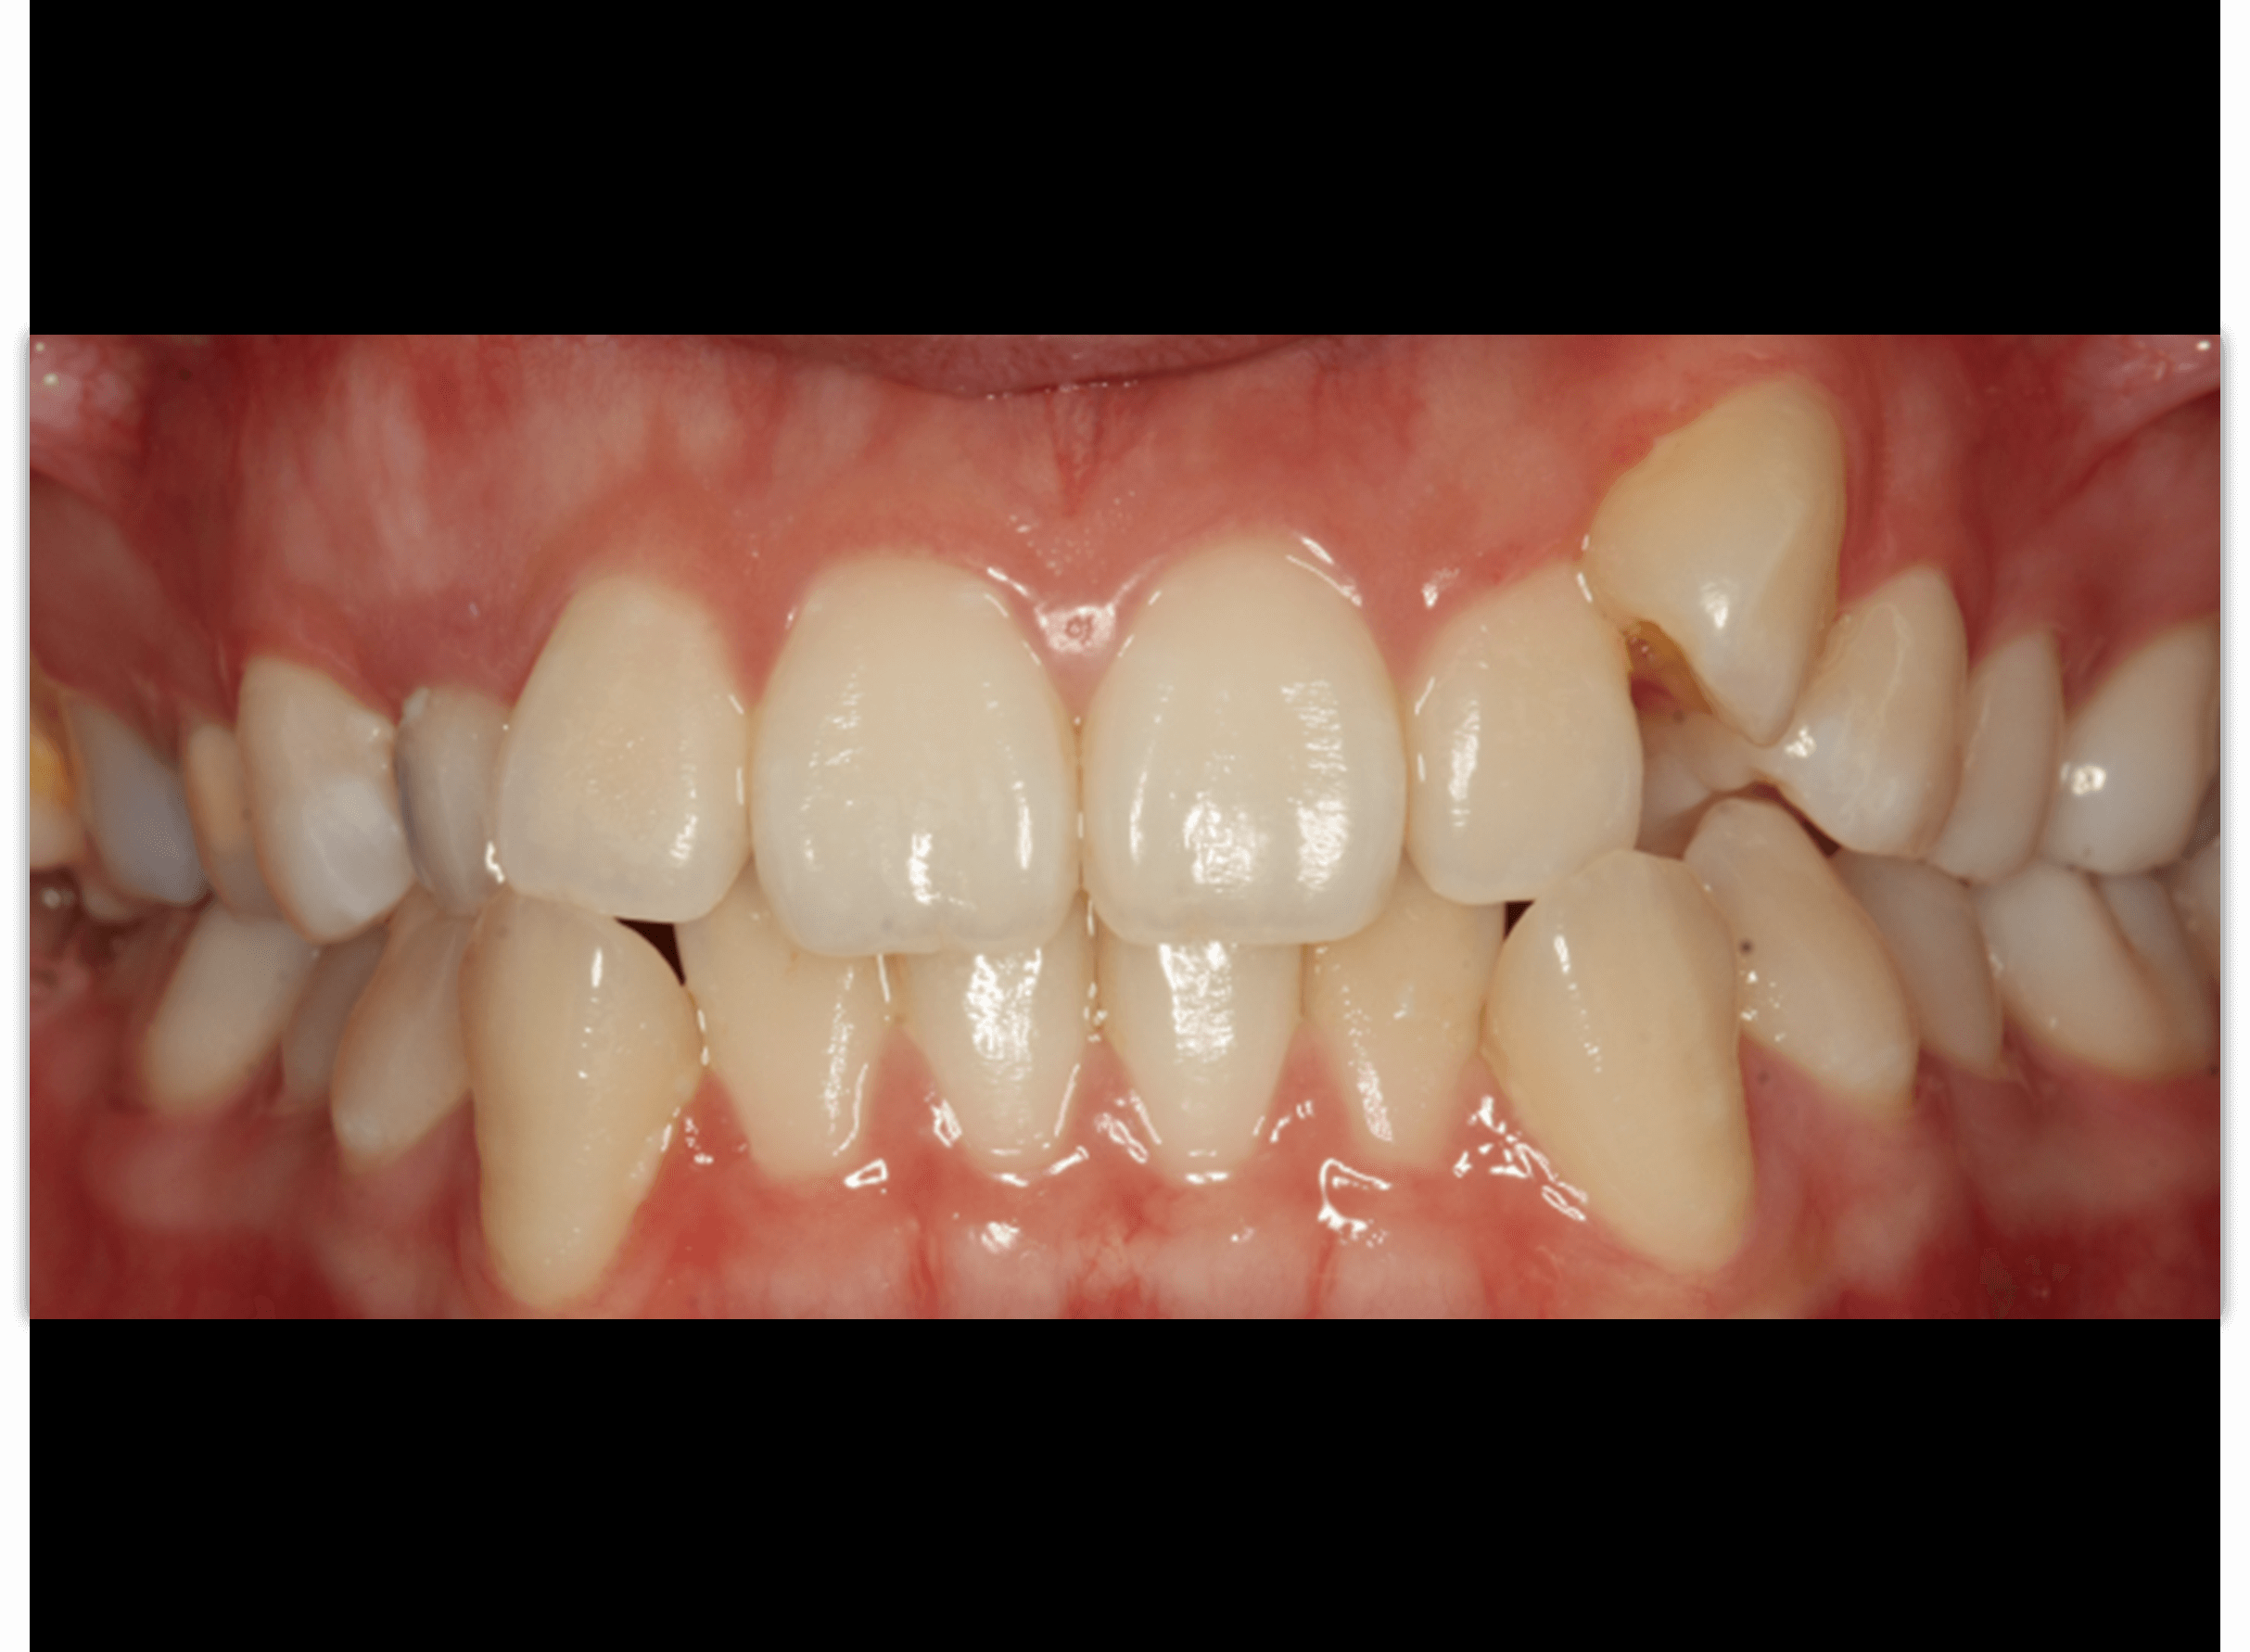

案例-8 首頁 案例分享 齒顎矯正 案例-8 牙齒矯正的改變,絕對值得您親自感受! 牙齒矯正是一條很不一樣的路 無法立即見效,但時間的推移 變美的路上有我們相陪! (圖片中使用的是"戴蒙矯正器") 齒顎矯正醫師:李慧凌 醫師